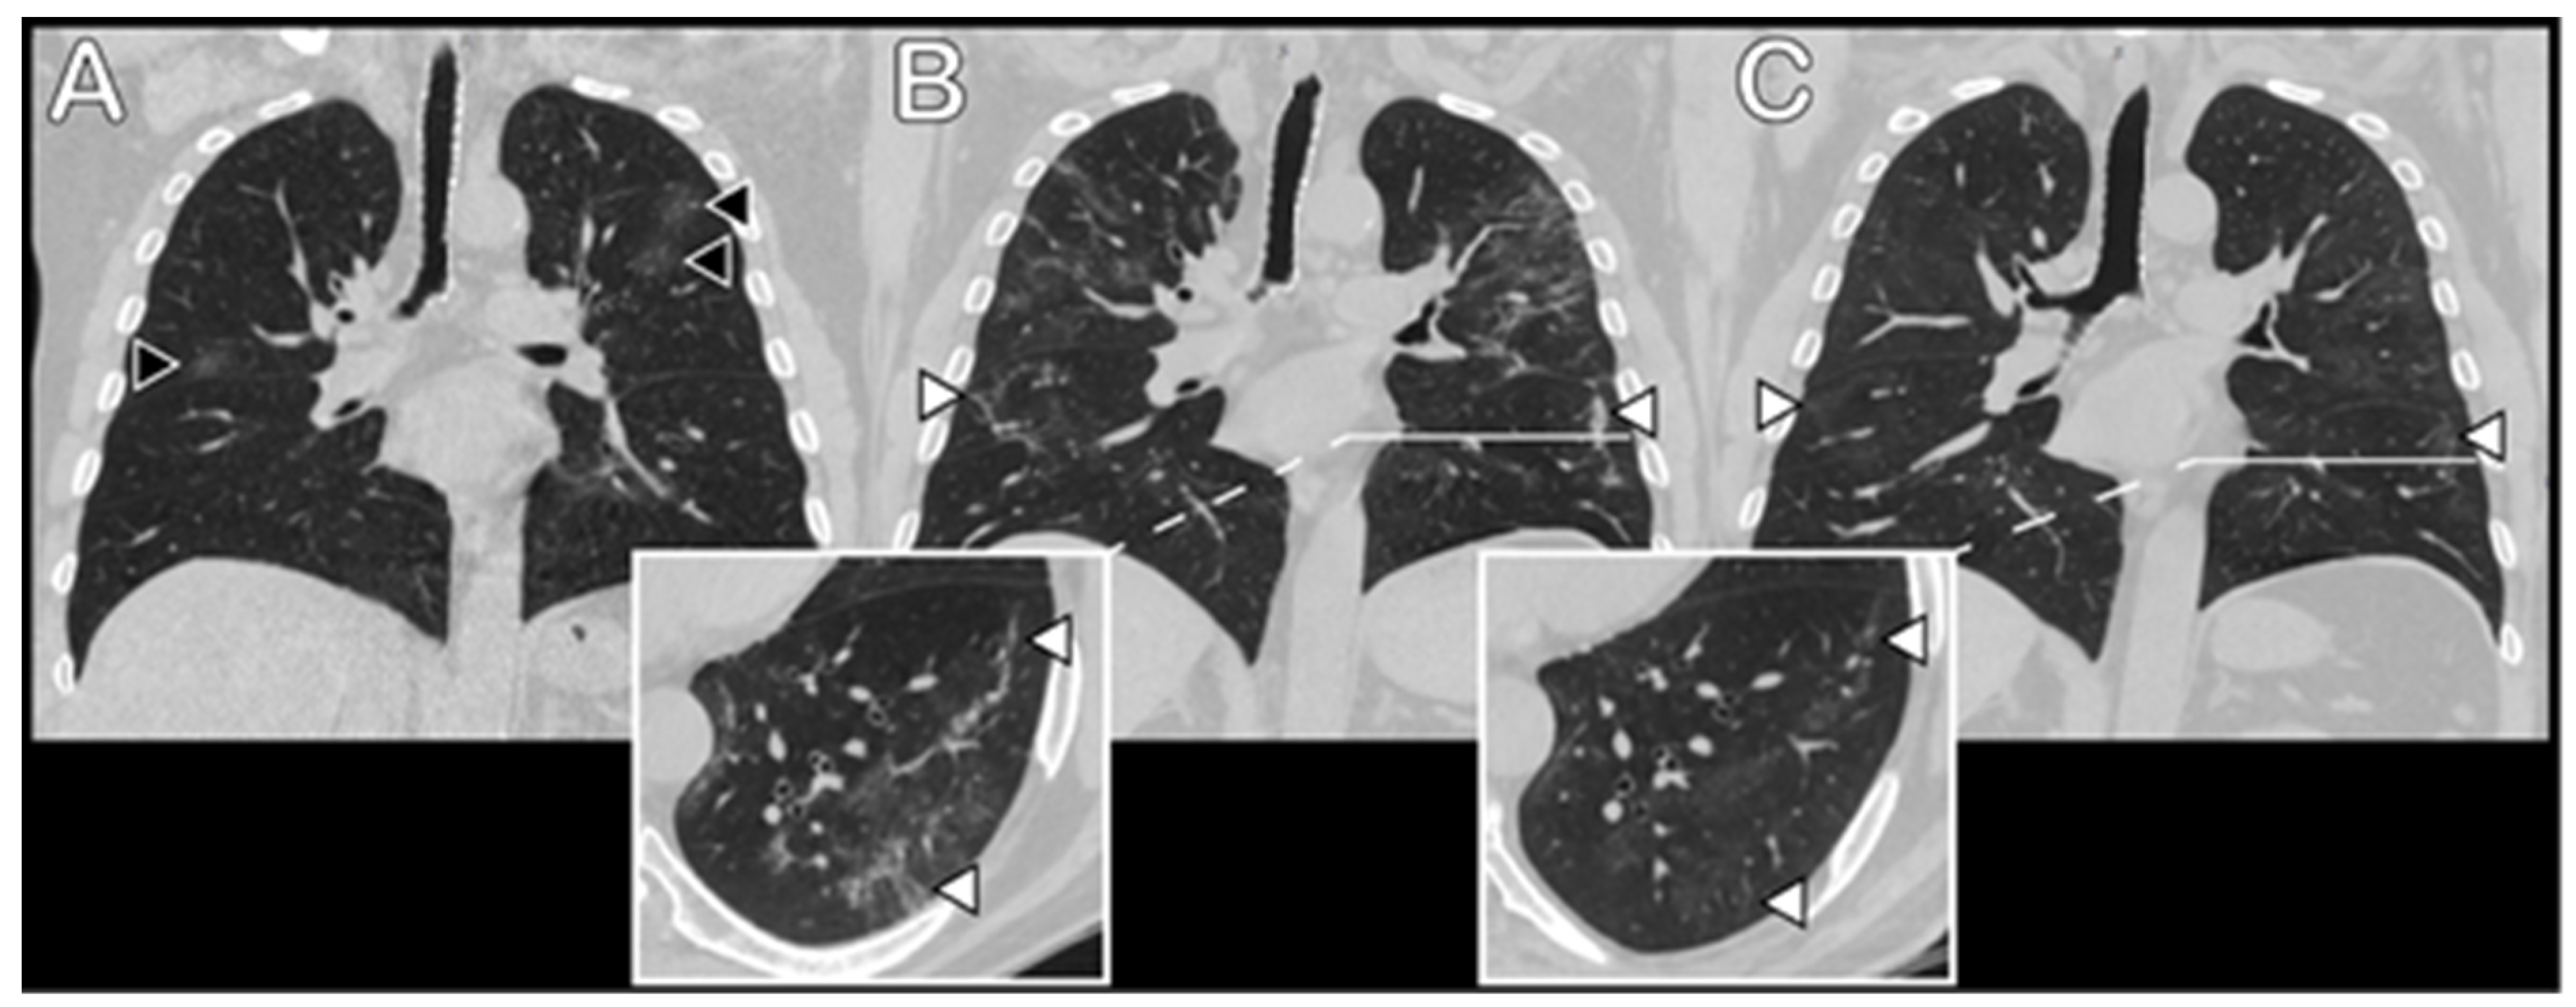

3.3. Radiological Data

3.4. Health-Related Quality of Life